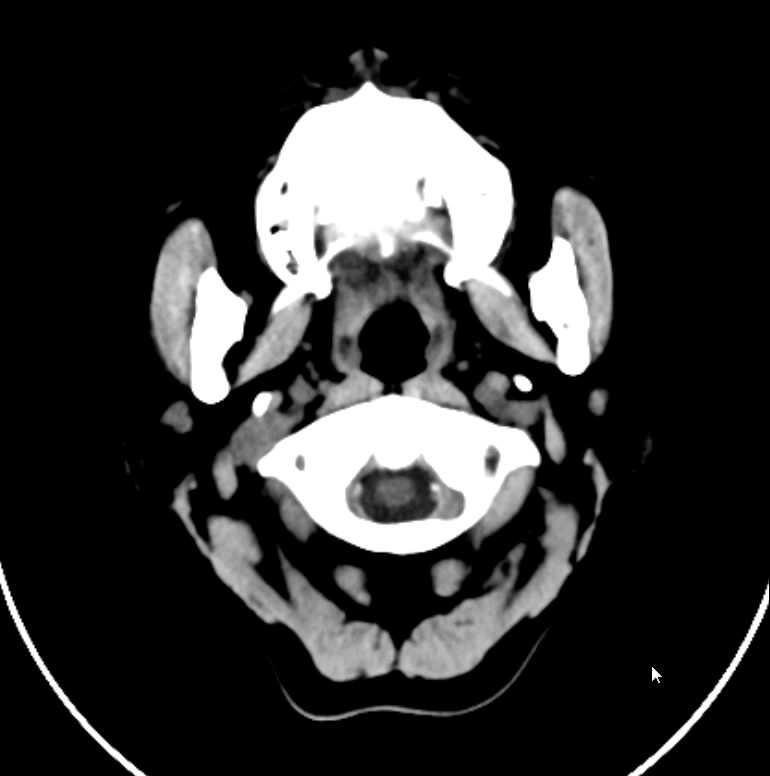

1、现病史:患者自诉,于10天前无明显诱因开始出现头痛、头昏、头晕,伴视物旋转,时感眼花,无耳鸣,伴咳嗽,无咳痰,头昏改变体位时加重,伴恶心、呕吐数次,呕吐物为胃内容物,无黑朦、意识障碍,感心悸、胸闷,无胸痛、呼吸困难,时感畏寒,未测体温(具体体温不详),发病后在村卫生室输液治疗4天(具体用药及剂量不详),症状无任何好转,今日为求进一步系统诊治,遂到我院门诊就诊,门诊医师完善颅脑及颈椎CT后以“头晕?头痛?”收住我科。病程中,精神、饮食、睡眠差,大小便肉眼未见异常,体重变化不详。

4、辅助检查:(2024-06-20)入院心电图示:窦性心律,心率79次/分。入院空腹血糖为:15.5mmol/L。(2024-06-20)入院血常规及超敏C反应蛋白示:白细胞计数:46.11x10^9/L↑↑;中性粒细胞绝对值:33.47x10^9/L↑;淋巴细胞绝对值:4.01x10^9/L↑;单核细胞绝对值:7.10x10^9/L↑;嗜酸性粒细胞绝对值:1.48x10^9/L↑;淋巴细胞百分比:8.70%↓;单核细胞百分比:15.40%↑;红细胞计数:3.19x10^12/L↓;血红蛋白浓度:91g/L↓;红细胞压积:27.5%↓;血小板:87x10^9/L↓;血小板压积:0.09%↓;大型血小板细胞数:22x10^9/L↓;C反应蛋白:6.66mg/L;糖化血红蛋白:10.3%↑;入院尿液分析示:尿胆原:+1;蛋白质:+2;尿白细胞:+3;葡萄糖:+-;比重:1.030↑;维生素C:+2;

1、头痛、头昏查因—1)脓毒症?2)血液系统疾病待排;3)急性脑梗死(脑干?小脑?)4)其它待排;2、2型糖尿病伴血糖控制不佳;3、2型糖尿病性肾病?4、社区获得性肺炎;5、泌尿道感染;6、冠心病待排;7、轻度贫血原因待查;8、血小板减少;9、电解质代谢紊乱?